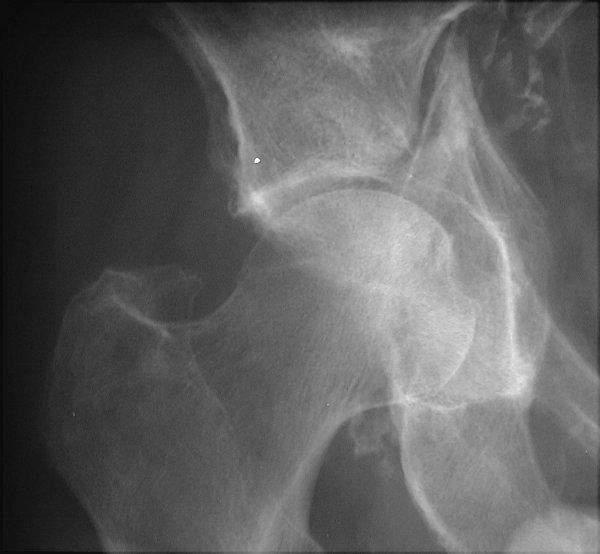

Return to Dashboard Fracture